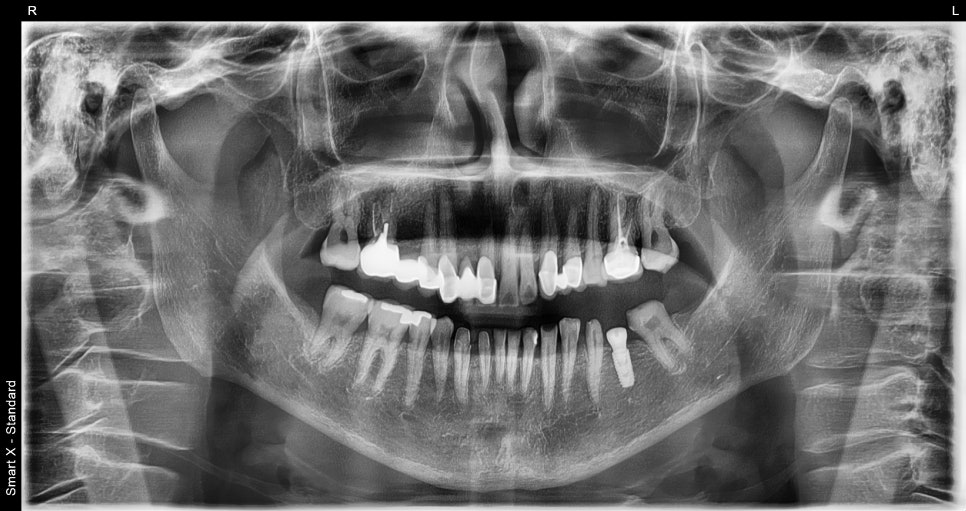

Final panoramic X-ray

➤ Final treatment photos

This shows the implant placed in the molar area and the crowns completed afterward. With colors and shapes harmonious with the natural teeth, both function and aesthetics were restored.